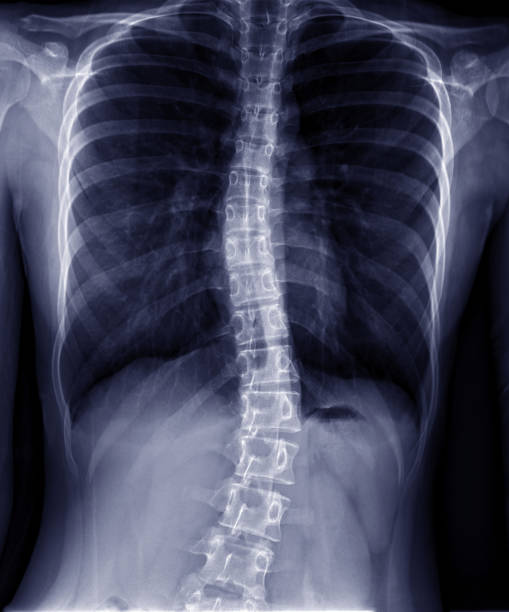

Die Ursache der Skoliose, die oftmals durch das Längenwachstum im Jugendalter besonders offensichtlich wird, ist der asymmetrisch tonische Nackenreflex (ATNR). Die einseitige Tonuserhöhung durch den ATNR zieht den Rücken allmählich in diese Fehlstellung.

ATNR: Die Kopfdrehung nach links bewirkt eine Tonuserhöhung im Besonderen der Extensoren der linken Körperseite. Gleichzeitig kommt es zu einer Tonuserhöhung der Flexoren auf der rechten Körperseite, die einhergeht mit einer Seitneige der Wirbelsäule nach rechts und zu einer linkskonvexen Skoliose führt. Dazu kommt die Torsion der Wirbelkörper mit dem Rippenbuckel auf der linken und dem Rippental auf der rechten Körperseite.